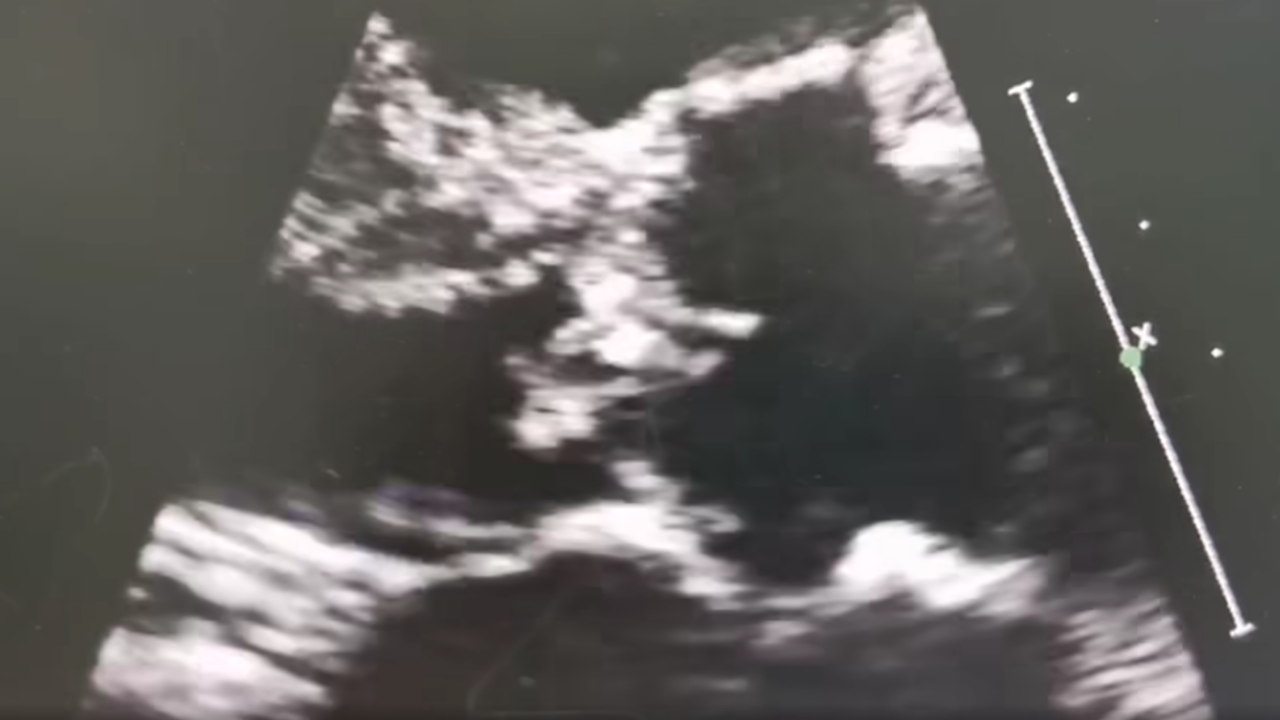

ตัวอย่างเคสนี้ที่เห็นนี้ คือเชื้อโรคเกาะกันเป็นก้อน (Vegetation) ที่ลิ้นหัวใจ Aortic Valve แล้วกินเนื้อเยื่อ จนทะลุ (Valve perforation) ทำให้น้ำท่วมปอดทันทีทันใด และต้องใส่ท่อช่วยหายใจเพื่อช่วยชีวิต ตอนนี้ต้องให้ยาฆ่าเชื้อ และรอผ่าตัดเปลี่ยนลิ้นหัวใจเทียม